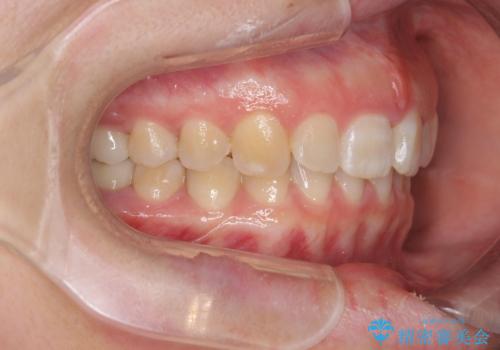

ねじれた前歯を改善するマウスピース矯正

- 大きくねじれた前歯をまっすぐに並べたい。と矯正治療を希望され来院されました。

前歯をきっちり並べるには奥歯の噛み合わせの調整を行い上下の前後的関係を治し、ねじれを取るスペースを確保していきます。

当初前歯だけ治れば良い、という心算で来院されましたが奥歯の噛み合わせも負担が大きく問題の起きやすいことをお伝えし上顎の奥歯をきっちりと後方移動行い噛み合わせの調整を行いました。・